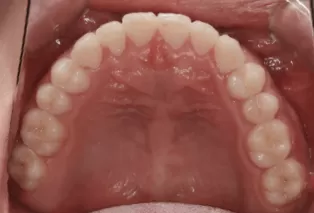

Photos intra-orales après traitement